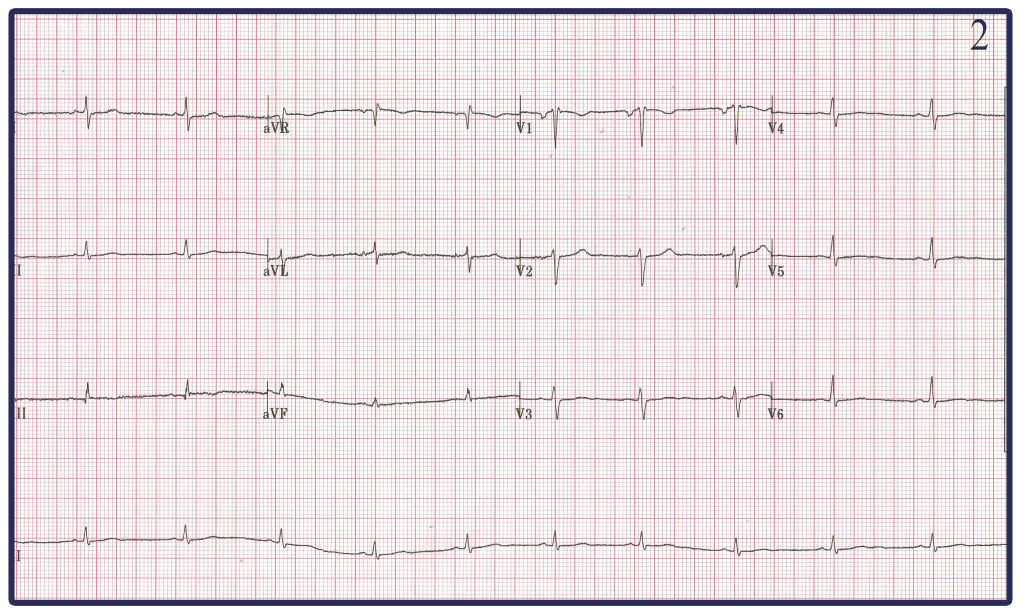

Here we see 5 electrocardiograms. All were done on the same person (a brilliant and handsome 41 year old EM physician) at the same time. There are clearly differences among them. One of them is ‘correct.’ To get you started, these are lead reversals.

-Both EKG 1 and 2 are more of a mystery to me. Honestly looking at EKG 2 and it appearing to be low voltage I would have assumed this to be caused by someone Obese. However I happen to know this 41 year old EM Physician (beauty is in the eye of the beholder) and would not consider him Obese. My best guess is that one of the leads in EKG 1 and EKG 2 was exchanged with the negative terminal RL changing the morphology of not only the Limb leads but also the chest leads in both.